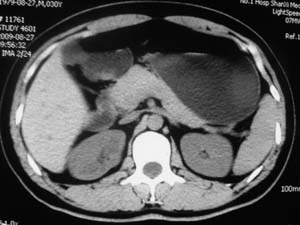

以下是引用子期在2010-3-19 20:47:00的发言:[br]血管畸形的ct增强应该有明显强化,本例并不相符合。本例双肾局部的略低密度影,累及肾盂,局部皮质明显变薄、内陷,增强扫描有轻度的强化,应考虑为炎性病变,患者为年轻男性,累及双肾的感染以结核较常见,可以没有明显的临床症状,尿中有时候也并不能查出什么;肾脓肿常有明显感染中毒症状,本例不符,另外一般的肾盂肾炎或肾小球肾炎通过小便就可确诊,其它还不能排除的是黄色肉芽肿性肾盂肾炎,然而单凭ct一般也很难鉴别。